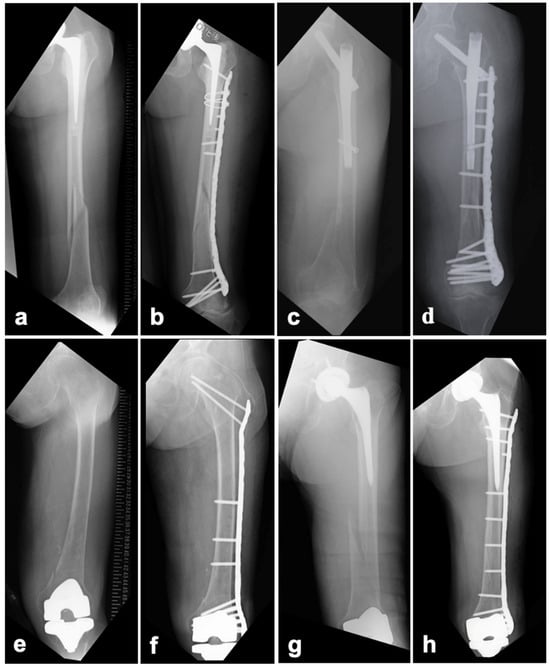

2.3.1. BHA/THA

2.3.3. TKA

3. Results